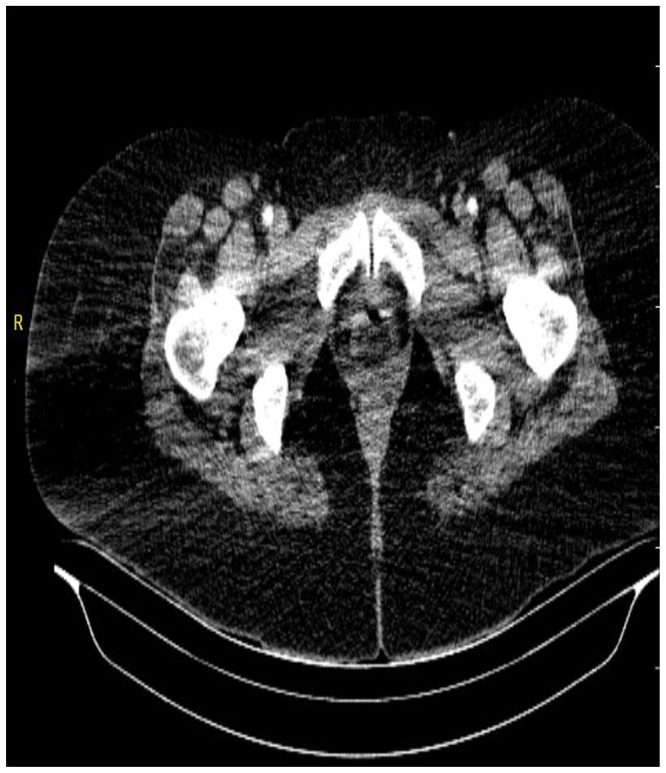

产后女性急性肢体缺血是一种罕见且严重的血管急症,如果不及时诊断和治疗,可能导致严重的并发症。31岁女性,采用取石位阴道分娩后30天,出现双侧下肢麻痹和感觉异常,分娩过程中无外伤、跌倒或辅助器械使用史。患者体重65公斤,身高162厘米,而婴儿的出生体重为2.8公斤。最初怀疑是神经系统疾病,后来通过影像学排除,包括胸腰椎MRI和CT血管造影,显示双侧动脉闭塞。尽管及时进行了血栓栓塞切除术,但由于进行性缺血,患者接受了双侧膝下截肢。本病例强调了产后急性肢体缺血的诊断挑战,强调了早期影像学和及时的多学科干预在预防严重后果中的关键作用。提高临床警惕性和及时调查对于改善预后和减少肢体丧失的风险至关重要。

Acute limb ischemia in postpartum women is a rare and severe vascular emergency that can lead to significant complications if not promptly diagnosed and managed. A 31-year-old woman, 30 days postpartum following uncomplicated vaginal delivery in the lithotomy position, presented with bilateral lower limb paralysis and paresthesia There was no history of trauma, falls, or use of assistive instruments during delivery. The patient weighed 65 kg and was 162 cm tall, while the infant had a birth weight of 2.8 kg. Initial suspicion of a neurological condition was later ruled out through imaging, including thoracolumbar MRI and CT angiography, which revealed bilateral arterial occlusions. Despite timely thromboembolectomy, the patient underwent bilateral below-knee amputation due to progressive ischemia. This case highlights the diagnostic challenges of acute limb ischemia in postpartum patients, stressing the crucial role of early imaging and prompt multidisciplinary intervention in preventing severe outcomes. Increased clinical vigilance and timely investigations are vital for improving prognosis and reducing the risk of limb loss.